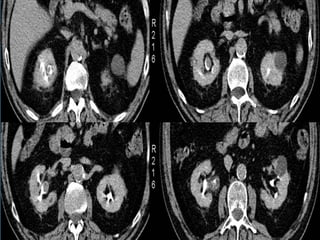

• #42 TUMOR UROTELIAL PIELOCALICIAL. Reconstrucciones coronales de TCMD en fase nefrográfica y en fase excretora que demuestran la existencia de una lesión neoproliferativa piélica derecha. La lesión presenta densidad de partes blandas y realza con contraste en FN, mostrándose como un defecto y distorsión de la repleción en FE.

• #43 CARCINOMA DE CÉLULAS TRANSICIONALES PIÉLICO. Imágenes axial y coronal en FN que muestran formación sólida hipercaptante ocupando pelvis renal izquierda. En las imágenes axial y coronal en FE la lesión se identifica como un defecto de repleción.

• #44 CARCINOMA URETERAL DISTAL DERECHO. Imágenes coronales de TCMD que muestran tumoración sólida endoluminal ocupando uréter distal derecho (flechas).

• #45 CARCINOMA UROTELIAL MULTIFOCAL, ureteral izquierdo y vesical. A) Las RMP de TC muestran focos de engrosamiento tumoral afectando el uréter izquierdo proximal y distal además de proliferación sólida endovesical (flechas). B) Imagen axial que muestra tumoración endoureteral izquierda (flecha). C) Imagen ecográfica que nuestra la lesión sólida perimeatal izquierda (flechas). D) Imagen axial de TC que demuestra afectación vesical y ureteral inferior (flecha).